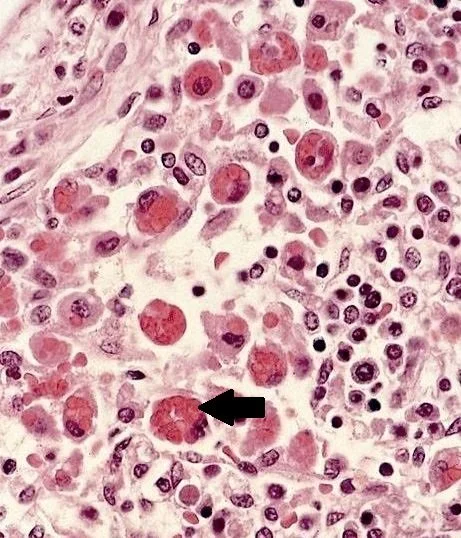

The slide shows atypical lymphocytes.  Since no diagnosis could be made a lymph node biopsy was done. It is shown below.

The lymph node biopsy showed a histiocyte (macrophage) in the process of phagocytosing RBCs. Does this represent hemophagocytic lymphohistiocytosis (HLH)?

HLH is a spectrum of disease  caused by dysregulation of the immune system where natural killer and cytotoxic T cells proliferate because they are unable to kill infected cells.  Infiltration of various organs of the body by mononuclear cells causes organ failure.  Histiocytes proliferate as well and  RBCs are phagocytized  resulting in anemia and cytokine activation.  A spectrum of the disease exists from a mild form to a massive cytotoxic storm. Specific criteria have been developed  for HLH which include genetic testing for those with the familial form; referred to as primary HLH.